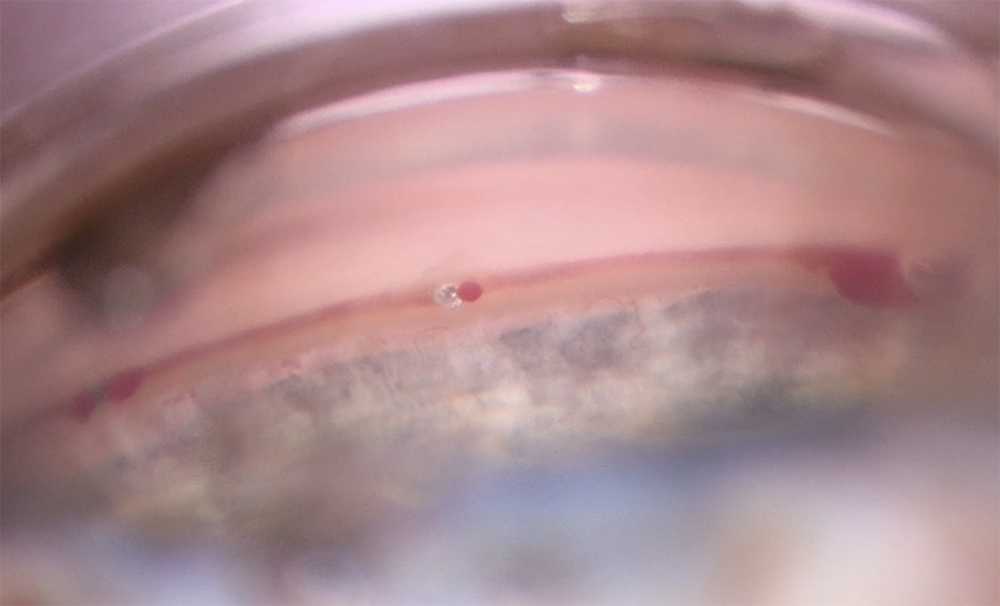

Source: Inder Paul Singh, MD

Source: Deborah Ristvedt, DO